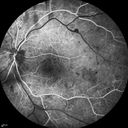

Proliferative Diabetic Retinopathy - Moderate - mild NVD with NVE 428 viewsFA shows leakage from neovascularization and dark areas in periphery from non-perfusion     (0 votes)

Proliferative Diabetic Retinopathy - Moderate - mild NVD with NVE 484 viewsFA shows leakage from neovascularization and dark areas in periphery from non-perfusion     (0 votes)